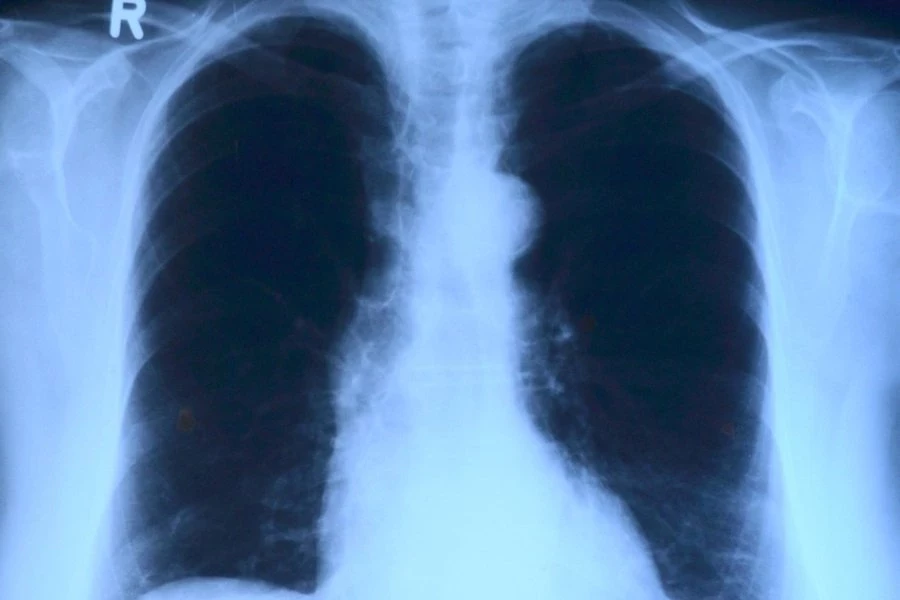

Искусственный интеллект теперь способен определить возраст человека, анализируя рентгеновские снимки грудной клетки. Эту новость сообщает журнал The Lancet.

Исследователи из Высшей школы медицины Осаки (Япония) протестировали модель искусственного интеллекта на 67 099 рентгенограммах грудной клетки. Эти снимки были сделаны в период с 2008 по 2021 год и принадлежали 36 051 здоровому человеку. Модель искусственного интеллекта успешно определила связь между предполагаемым возрастом, вычисленным на основе анализа ИИ, и реальным хронологическим возрастом людей. Коэффициент корреляции составил 0,95, что свидетельствует об очень сильной связи между этими показателями. Дополнительно эксперты использовали 34 197 рентгенограмм грудной клетки от пациентов, у которых уже были диагностированы различные заболевания.

Исследование показало, что разница между возрастом, определенным искусственным интеллектом, и хронологическим возрастом пациента была связана с определенными заболеваниями. Вероятность наличия гипертонии, гиперурикемии и хронической обструктивной болезни легких увеличивалась с ростом предсказанного возраста, полученного ИИ.